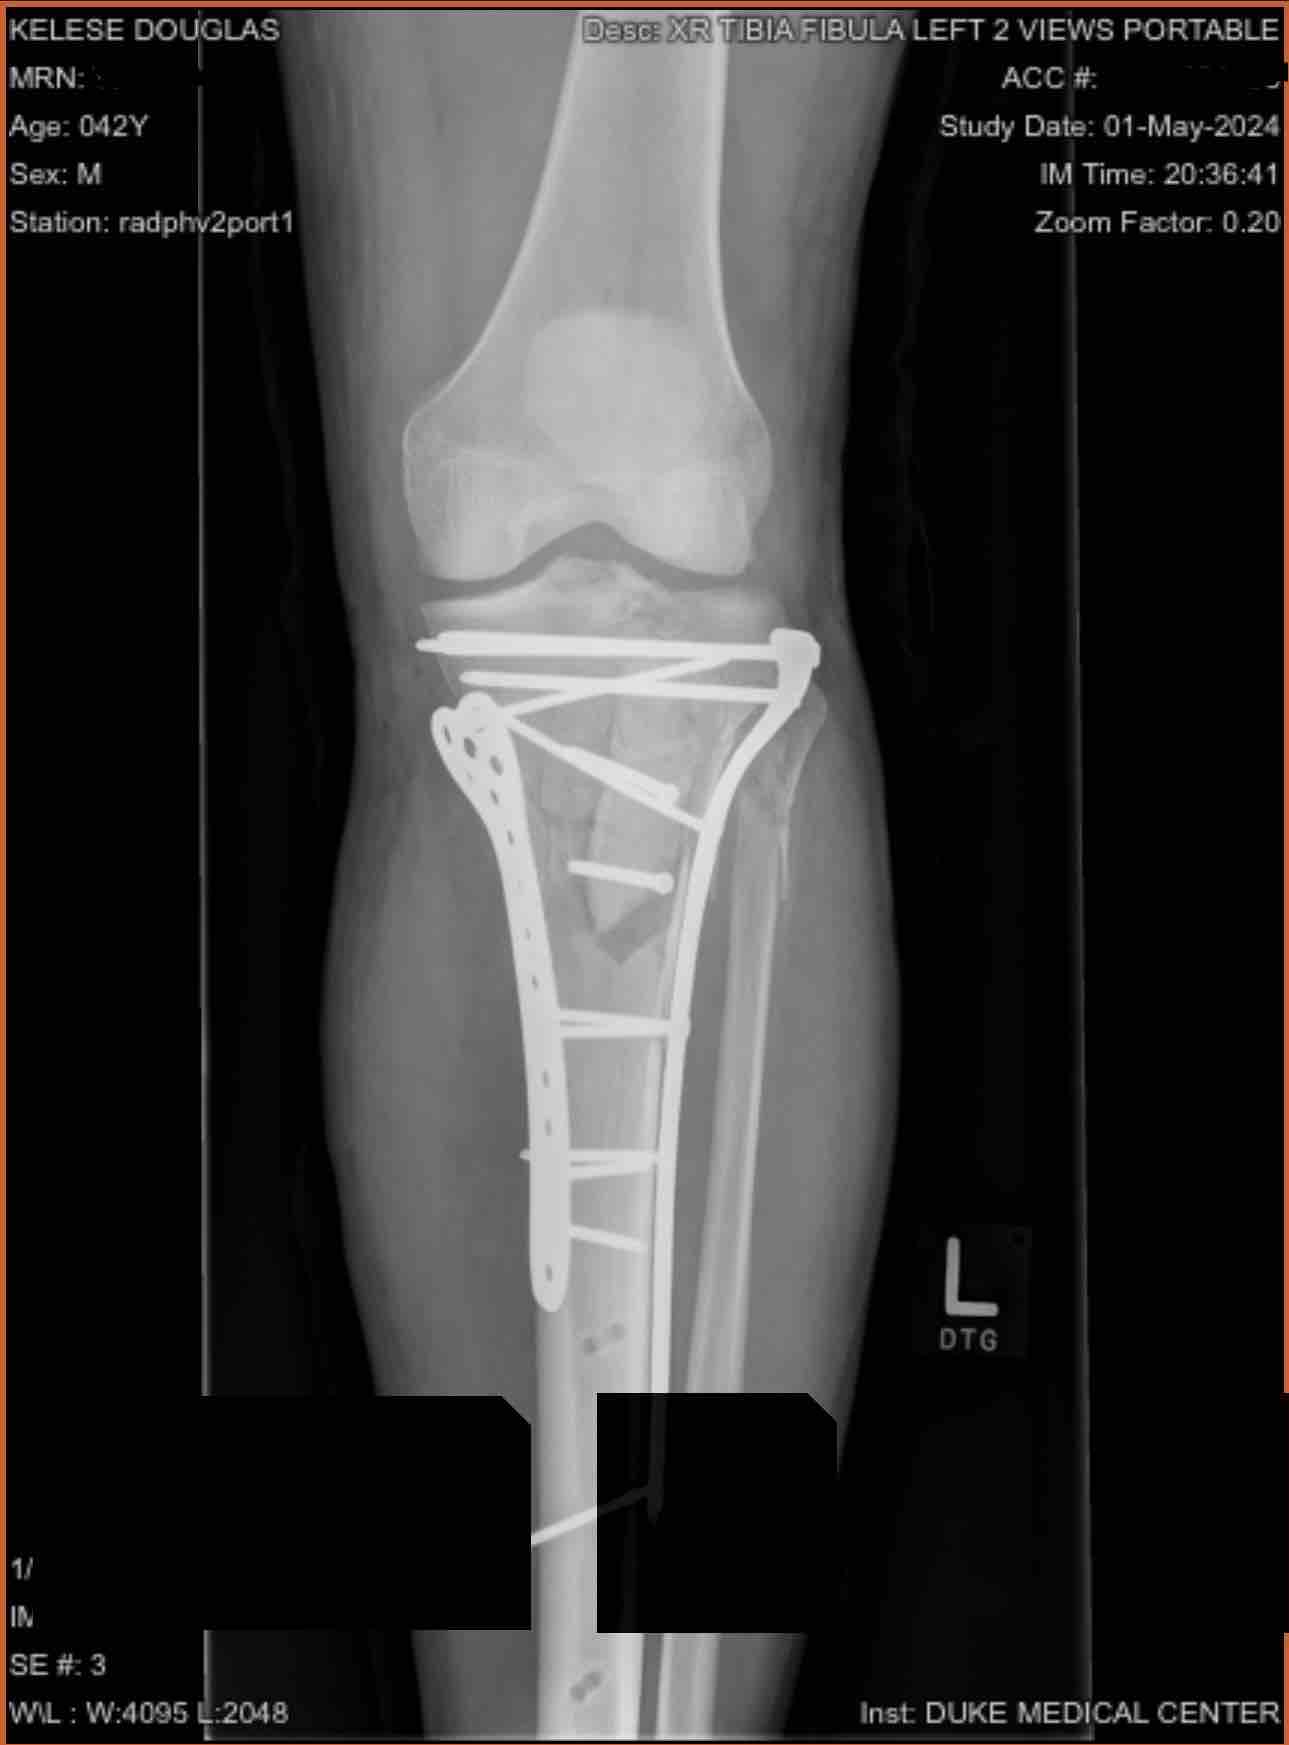

Hi, there, On April 6th, I was involved in a serious motorcycle accident with major injuries to my left leg. My tibia, the big bone in lower leg, was shattered at the knee joint. I’m facing a long road to recovery with multiple surgeries. I have already had one surgery to install a metal brace to keep my bones together while the swelling goes down. Soon I’ll have another surgery to repair my bone with multiple metal plates and screws. There will be months of physical and occupational therapy to learn to walk again.

secondary surgery was completed to install my pens and rods to stabilize my tibia. There was a few complications afterwards but eventually things got stabilized, and I was sent home to rest and recover but still a long ways until I can start physical therapy. Thank you again for your help in support.